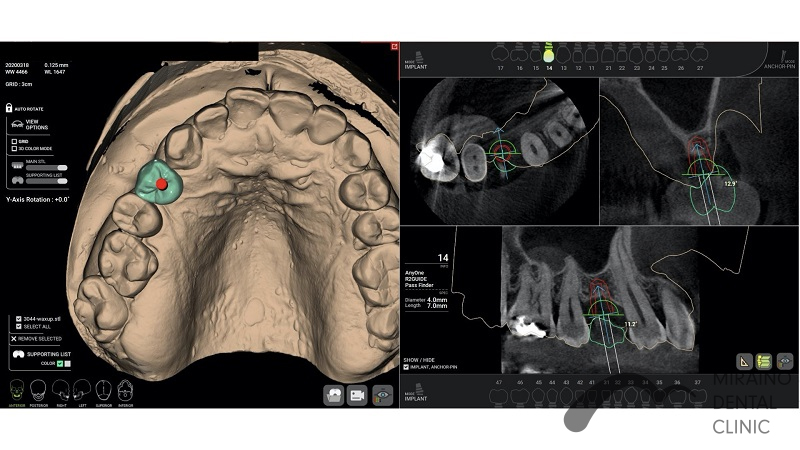

インプラントの症例

Case1

| 施術名 | インプラント |

| 施術の概要 | 10年前ほどに根の先に膿ができて抜歯。 前医では骨が少なくなってしまってインプラントは不可能ということで当院来院。 インプラントOPE時に仮歯まで作成し見た目の回復まで行いました。 その後OPE後3ヶ月で最終の被せ物装着する。 |

| 施術の内容 | インプラントは、従来の入れ歯やブリッジとは違い、天然の歯と同じような強くて、美しい歯を取り戻す治療法です。 失った歯の代わりに人工の歯根を埋め込み、その上に人工の歯を装着。 健康な歯を削ることなく、新しい歯が蘇ります。 2~3か月後に上部構造(歯の部分)を装着してかみ合わせを回復させます。 |

| 1歯あたりの治療費 | 450,000円(10年保証込) 骨が薄く造成が必要な場合は追加費用がかかります。 骨造成:30,000円~100,000円 |

| 考えられるリスク、副作用 | 疼痛・咬合時痛・腫脹や出血などを生じる事があります。 時間経過とともに治ります。 |

| 考えられるリスク、副作用[全てにおいて] | 必ずしもご希望通りの見た目にならない事があります。 |

| 考えられるリスク、副作用[麻酔] | 麻酔を行う場合、腫れやむくみを生じる事があります。 |

| 考えられるリスク、副作用[噛み合わせ] | かみ合わせの変化・違和感が生じる事があります。 |

| 考えられるリスク、副作用[被せ・仮歯] | 強い衝撃を与えると、被せ物が欠けたり割れたり、外れたりする事があります。 仮歯の期間中は仮歯の部分で噛むと破損する場合があります。 |

| 保証について | 治療後10年以内であれば再治療を行います。 喫煙、糖尿病、加齢、清掃不良などメンテナンスが不十分な場合、インプラント周囲炎になる事があります。 10年保証を受けるには当院にて年2回以上のメンテナンスが必要になります。 (メンテナンスはインプラント治療に関わらず、一般的にご自身の歯の場合でも必要であると思われます。) |